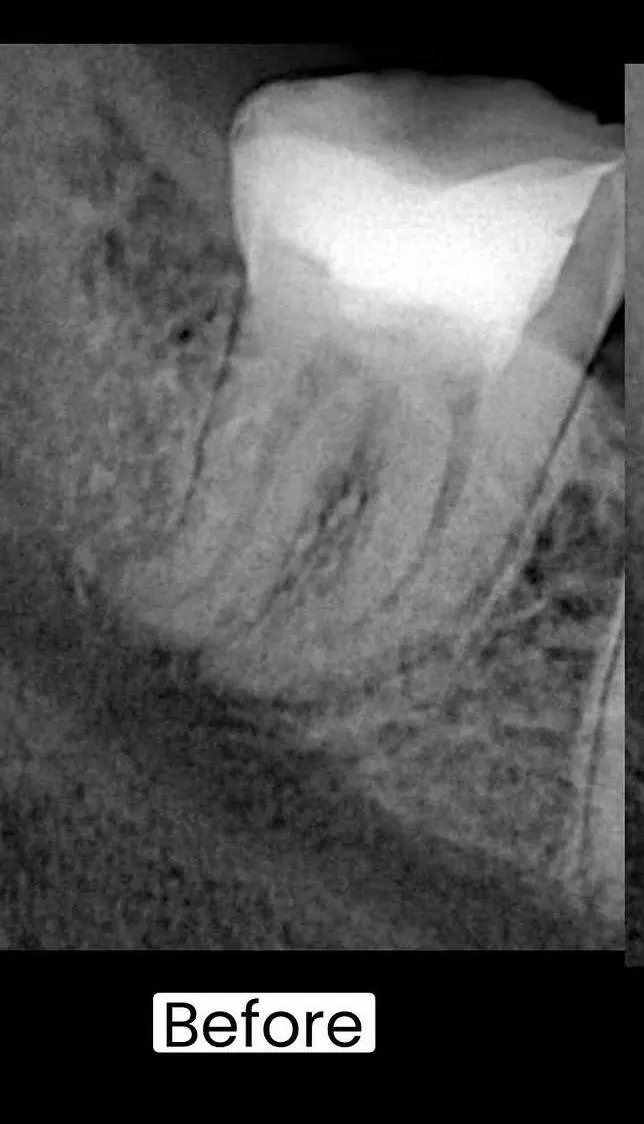

قبل